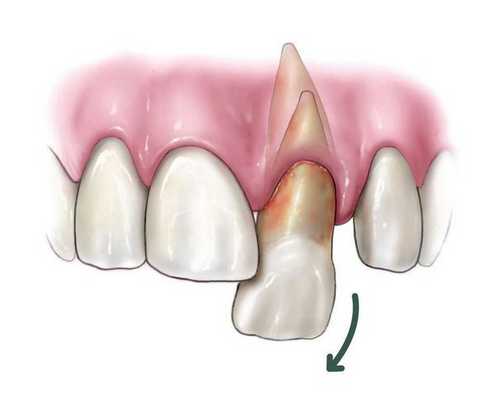

о Экструзивный вывих; корональное или язычное смещение с появлением гиподенсной лунки в области корня

о Экструзивный вывих:

- Сагиттальная плоскость:

Язычное и корональное смещение коронки зуба

Лицевое смещение корня зуба, обычно через лицевую кортикальную пластинку